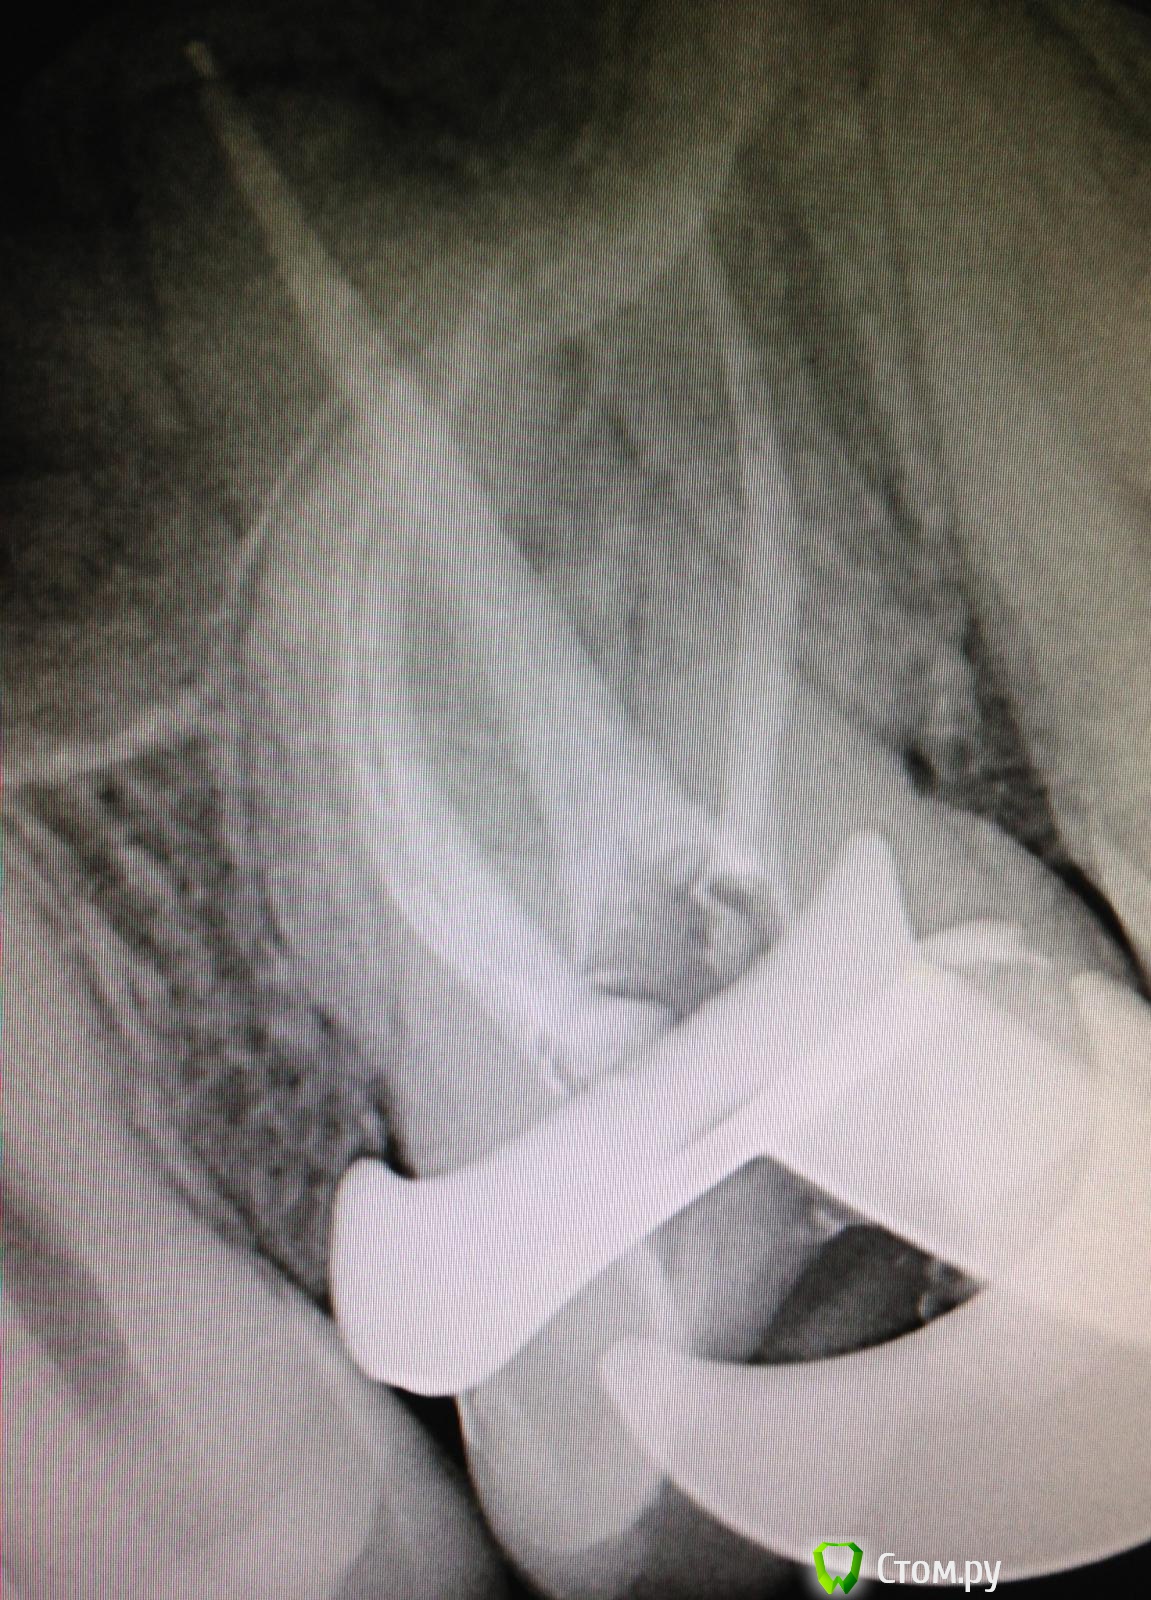

SSTi Опубликовано 22 ноября, 2014 Автор Поделиться Опубликовано 22 ноября, 2014 26. Хронический апикальный периодонтит. Пропущенный мб2. Зуб лечили год назад в гсп. Платно. И весь год он болел. Постоянные слабые боли. Переуссия +. 1 визит - коффердам, доступ, распломбировка мб, дб, небного. Поиск мб2. Обработка 4 каналов - протейпер д2,д3, профайлы - небный до 45.04. , мб и дб до 35.04, мб2 до 30.04. Гипохлорит, эдта, хлоргексидин, уз. Кальций. 2 часа. Второй визит - болей нет. Переуссия б/б. Вымыли кальций, еще моемся долго, латералка ( ан+ ). 2 часа. Ссылка на комментарий